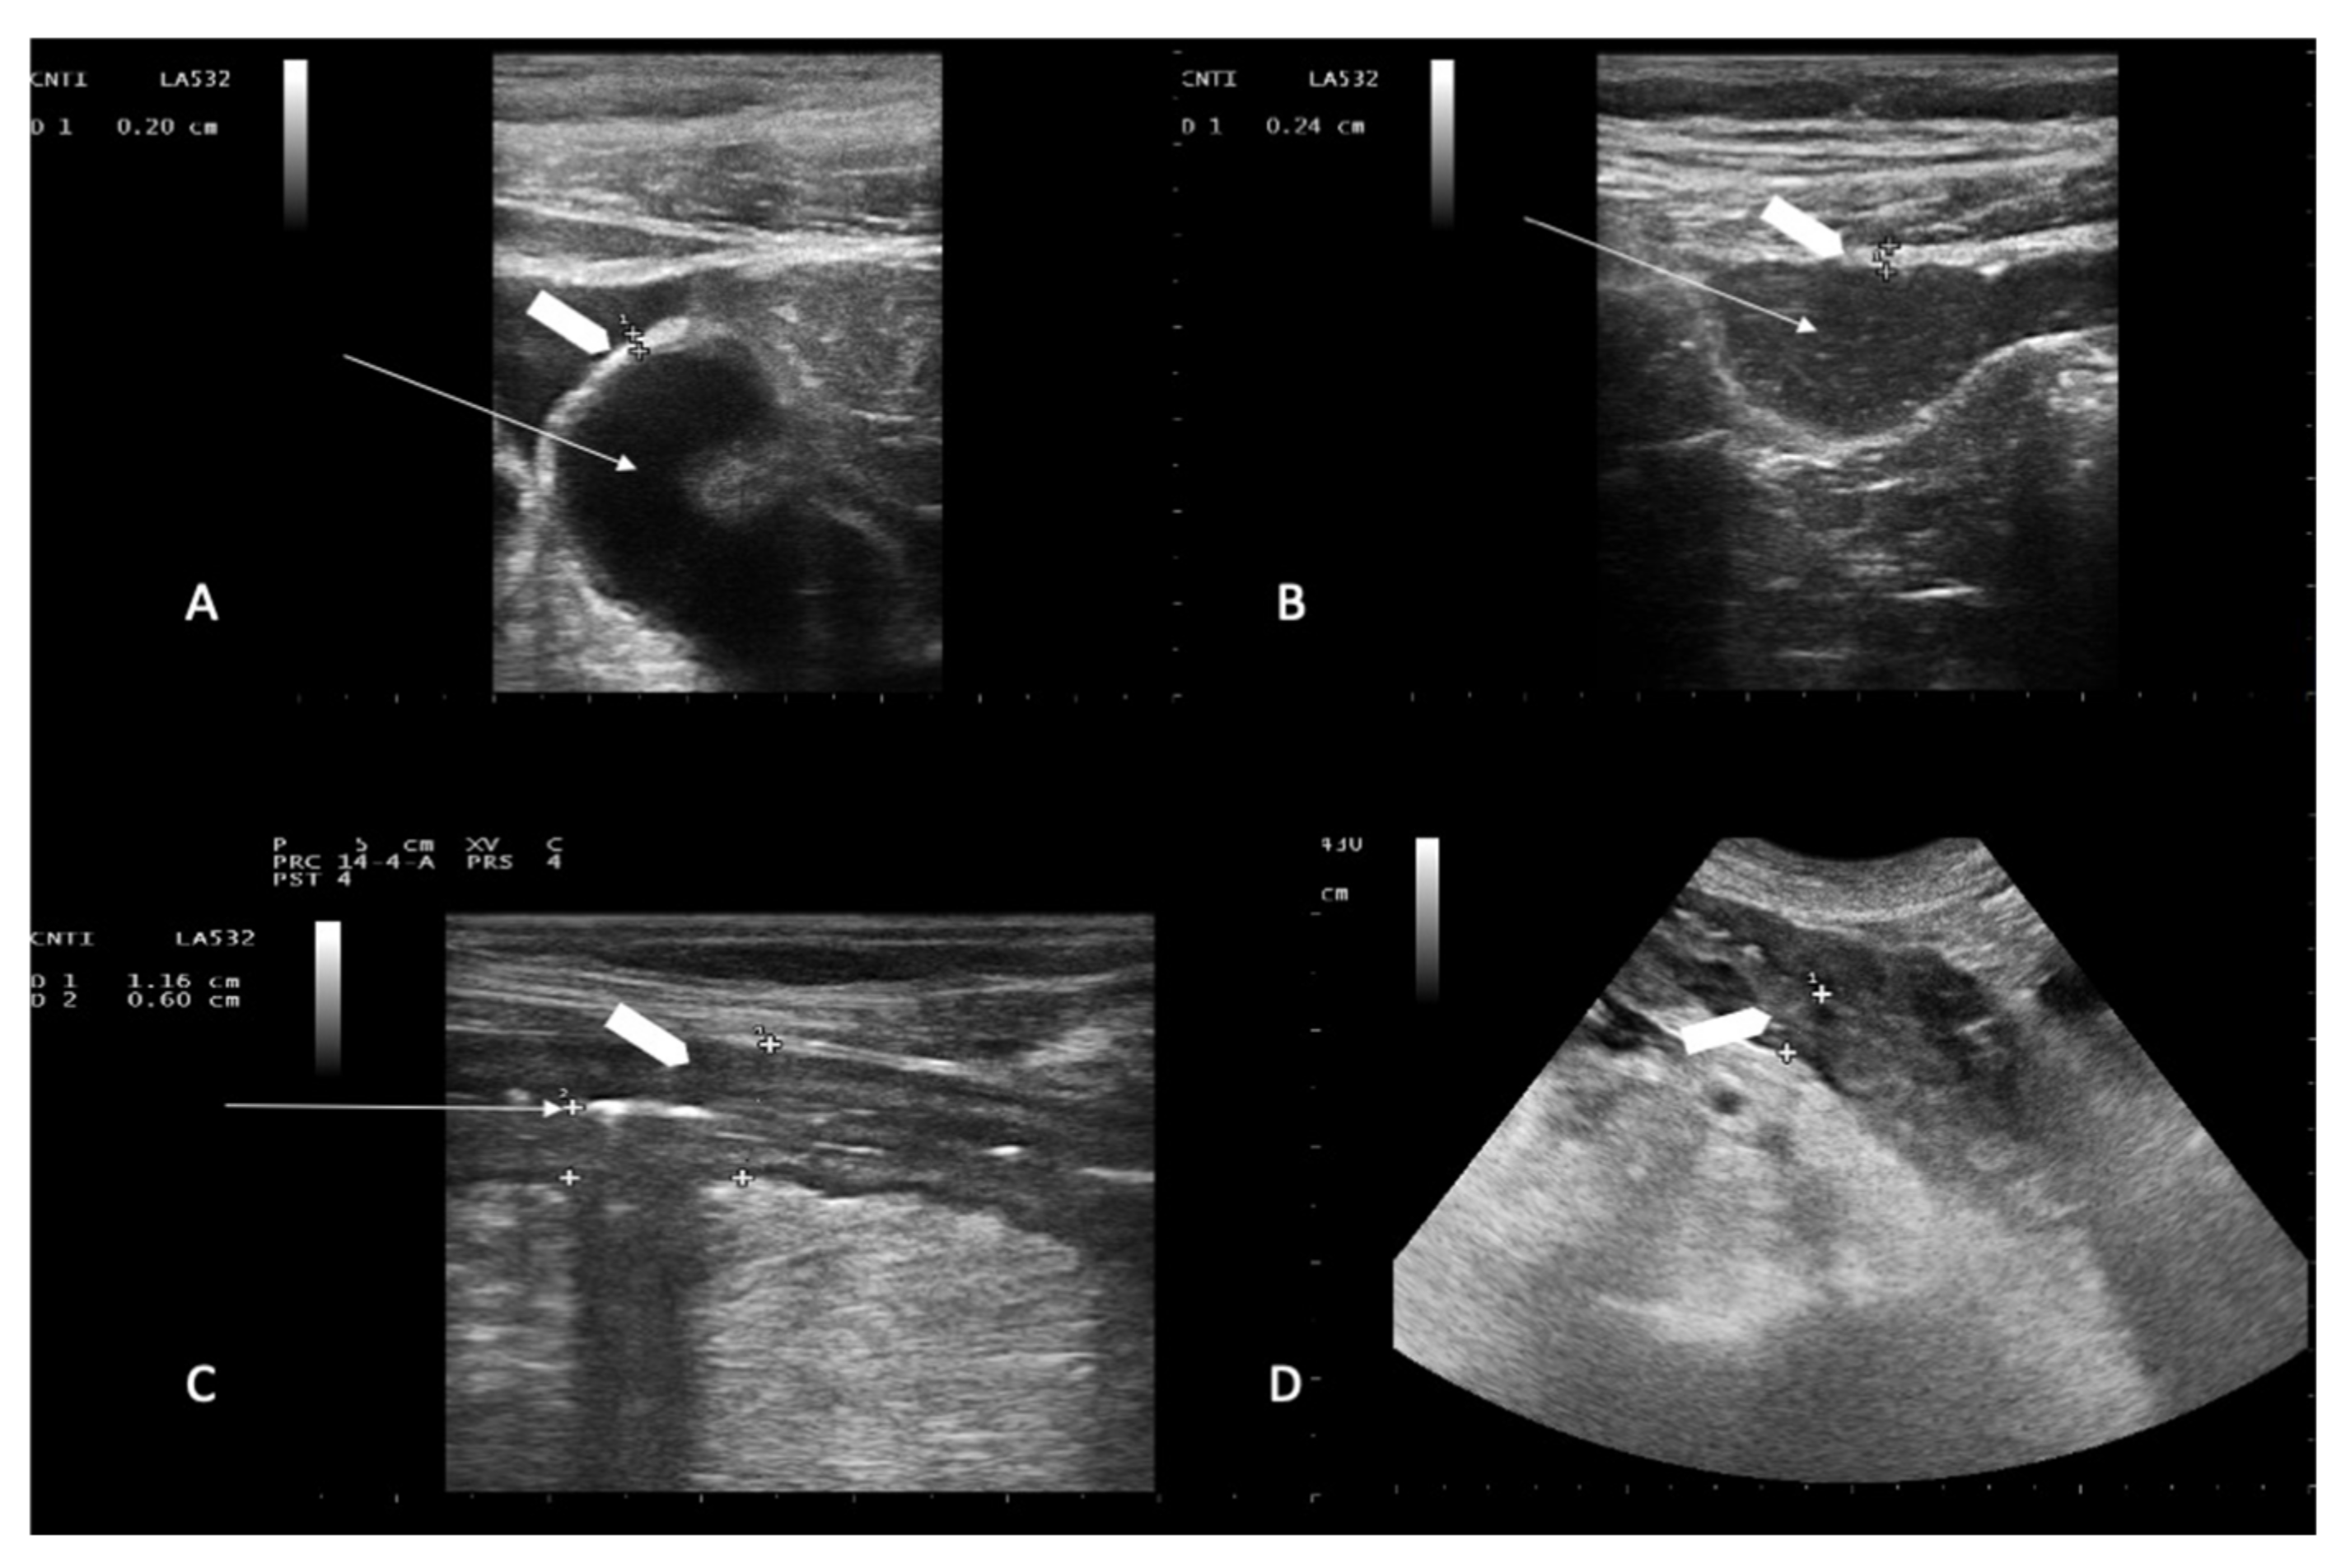

2.5. Ultrasonographic Examination

- Dietrich, C.-F.; Hermann, S.; Klein, S.; Braden, B. Sonographic signs of neutropenic enterocolitis. World J. Gastroenterol. 2006, 12, 1397–1402. [Google Scholar] [CrossRef]

- Benedetti, E.; Caracciolo, F.; Lippolis, P.; Bruno, B.; Caramella, D.; Cerri, F.; Simonetti, F.; Orciuolo, E.; Buda, G.; Pelosini, M.; et al. Neutropenic enterocolitis: Prospective study on usefulness of ultrasound sonography for early diagnosis and to guide medical or surgical treatment. Bone Marrow Transplant. 2012, 47, S77. [Google Scholar]

- Benedetti, E.; Lippolis, P.V.; Caracciolo, F.; Galimberti, S.; Papineschi, F.; Pelosini, M.; Focosi, D.; Stella, S.M.; Neri, E.; Seccia, M.; et al. Ultrasound findings guided a successful hemicolectomy in a leukemic patient with neutropenic enterocolitis. J. Ultrasound 2008, 11, 97–101. [Google Scholar] [CrossRef][Green Version]

- Cartoni, C.; Dragoni, F.; Micozzi, A.; Pescarmona, E.; Mecarocci, S.; Chirletti, P.; Petti, M.C.; Meloni, G.; Mandelli, F. Neutropenic Enterocolitis in Patients With Acute Leukemia: Prognostic Significance of Bowel Wall Thickening Detected by Ultrasonography. J. Clin. Oncol. 2001, 19, 756–761. [Google Scholar] [CrossRef] [PubMed]